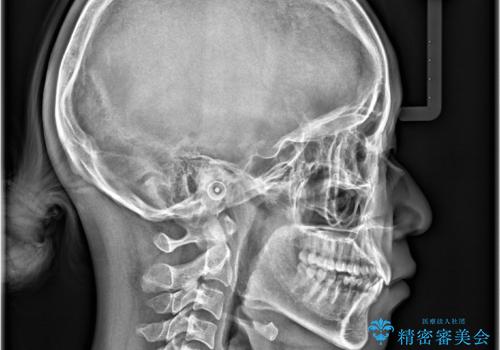

非抜歯矯正で八重歯を改善|短期間8か月で美しい歯並びに|インビザラインライト上顎のみで矯正

- 「八重歯を治したい」との主訴でご来院された患者様です。。

非抜歯で上顎のみインビザラインライトを使用して矯正を行いました。